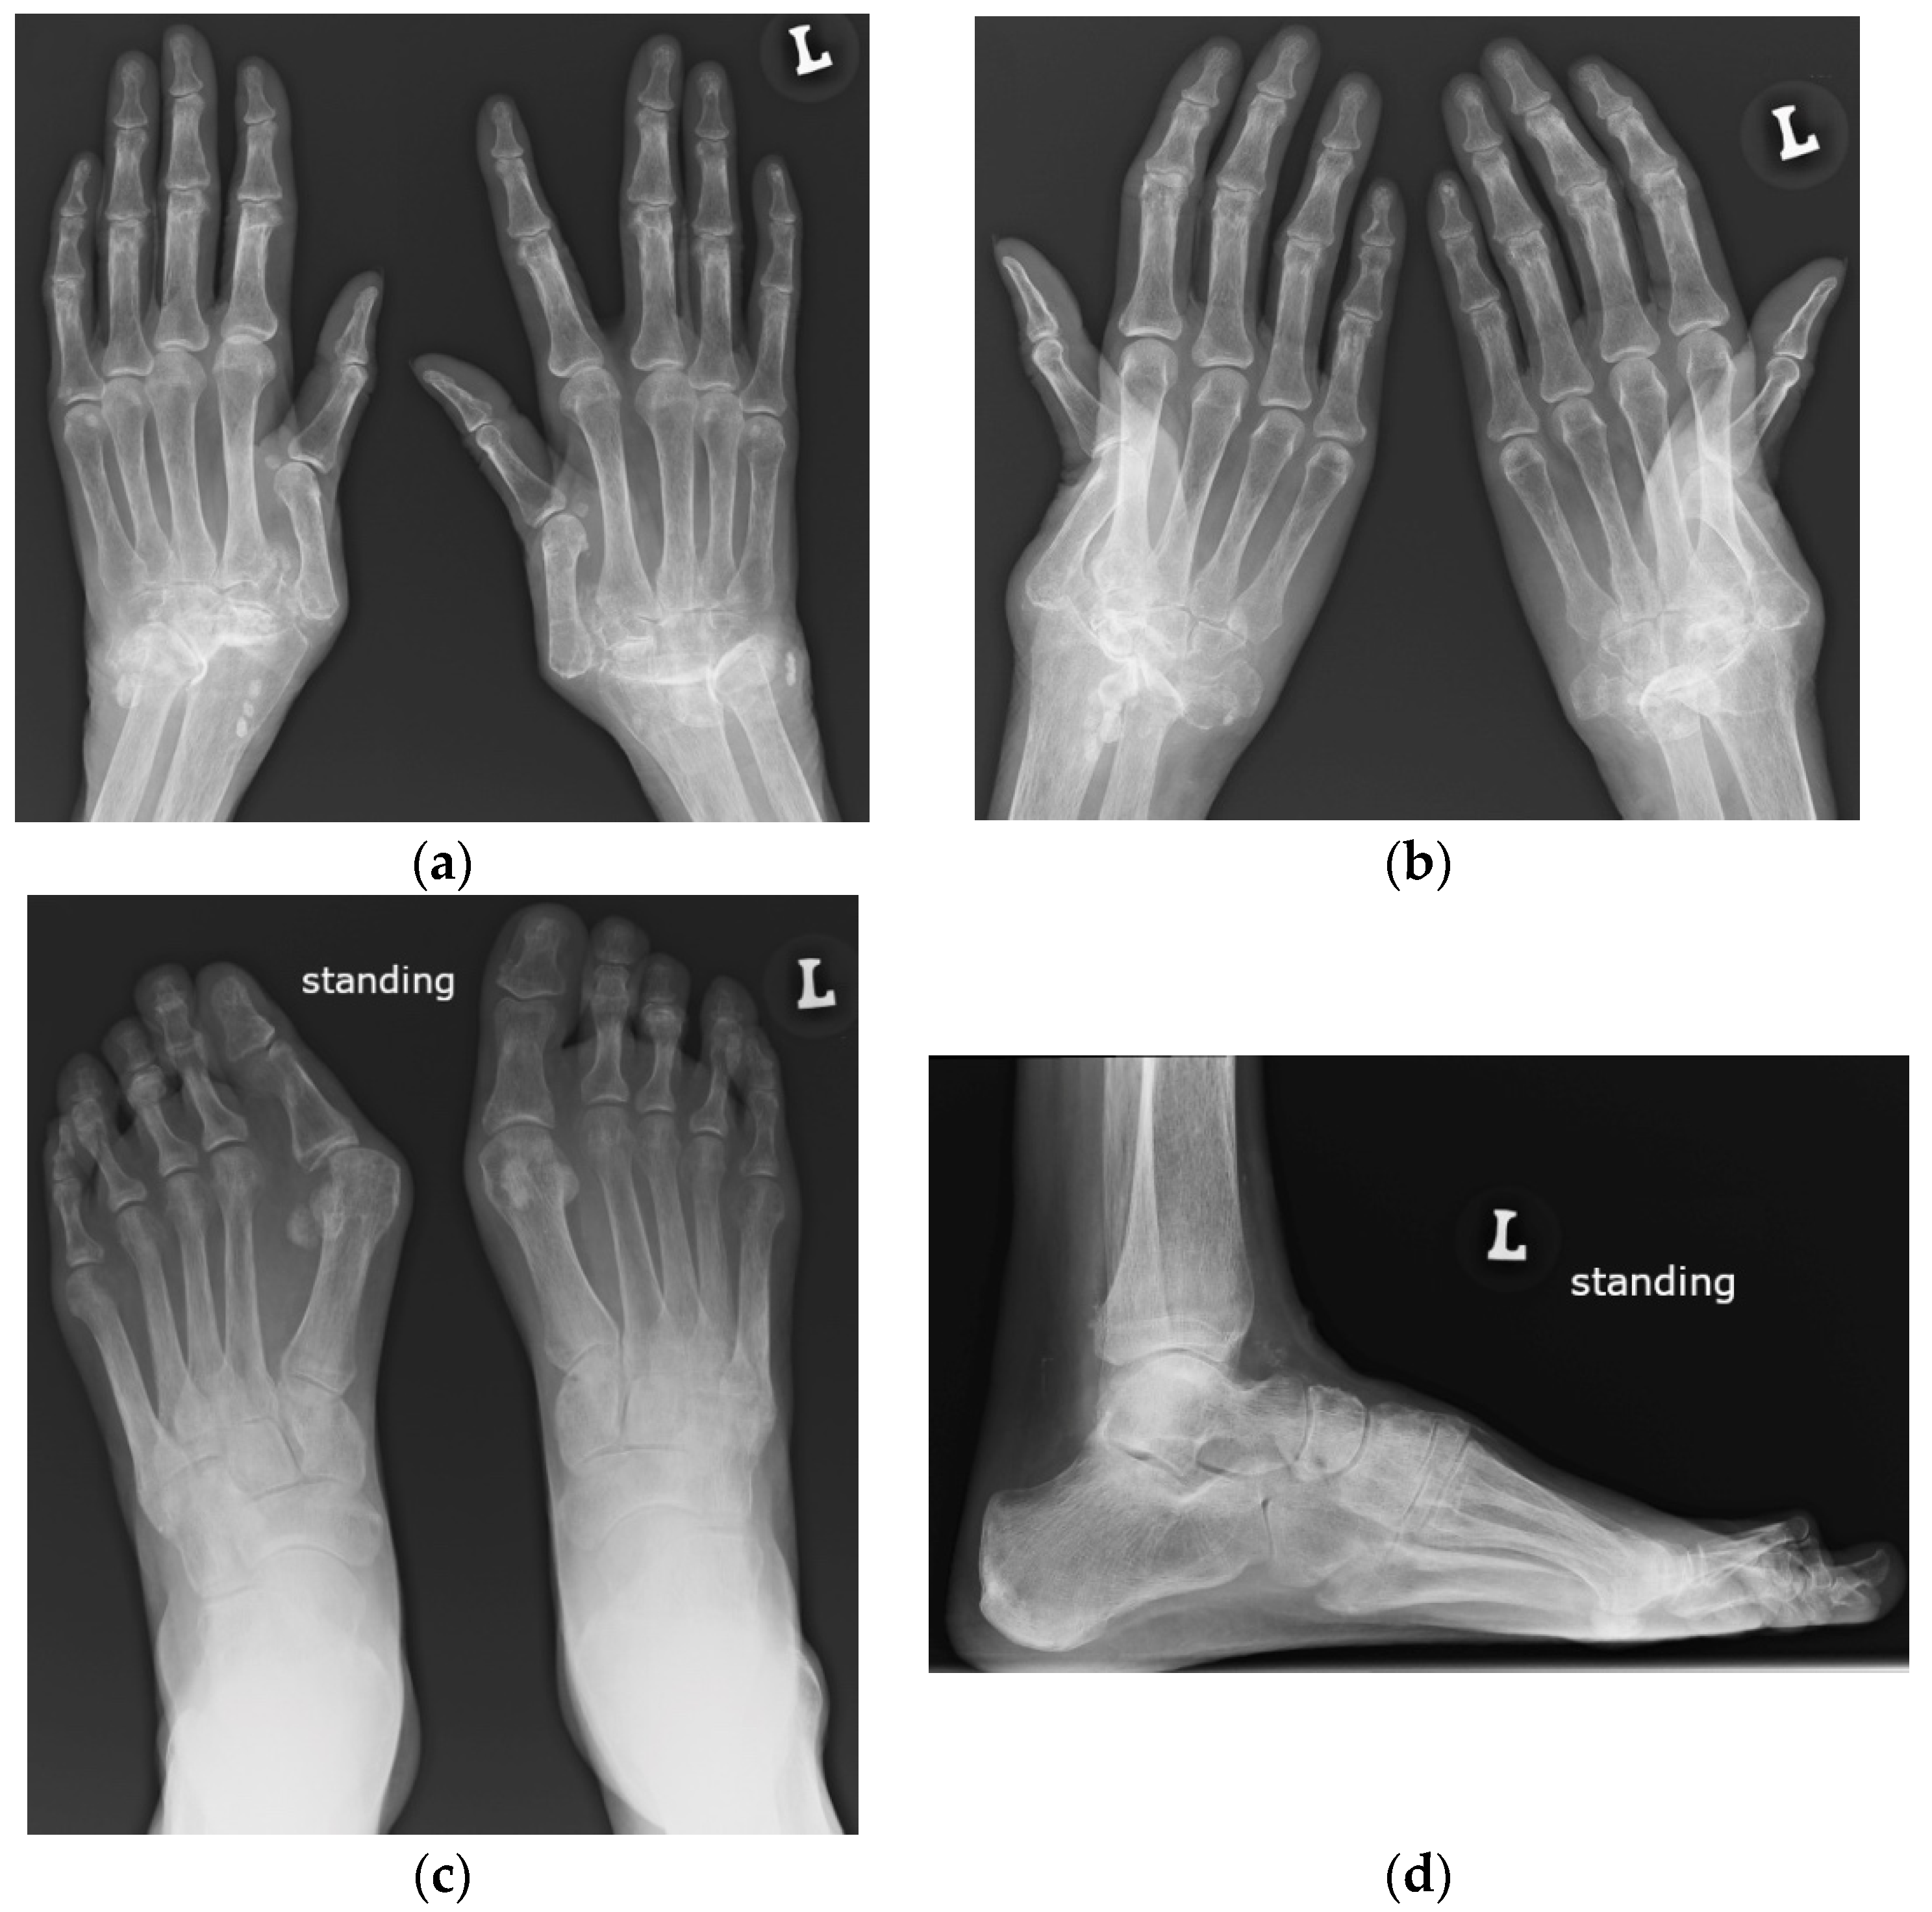

Figure 6.

A complete spontaneous tear of the right posterior tibialis tendon (PTT) 2 cm above the medial malleolus in a 46-year-old female with systemic lupus erythematosus. (a,b) short-axis gray-scale ultrasound (US) images of the medial aspect of the bilateral ankles show the normal echogenic fibrillar appearance of the healthy left PTT (a, arrow) compared to an enlarged, torn right hypoechoic PTT in the same region between calipers in (b). (c) Short-axis power Doppler US image of the affected right side shows hyperemia in the PTT tendon stump, with additional hyperemia in the tendon sheath consistent with tendinopathy and tenosynovitis. Two tiny red dots at the periphery of green Doppler box represent normal vessels.

Figure 7.

A complete tear of the proximal part of the bare tendon of the distal biceps brachii bilaterally in the same patient as in Figure 6. Short-axis (a,b) and long-axis (c,d) gray-scale ultrasound images of the bilateral elbow/distal arms show rupturing of the bilateral distal biceps tendons at the level of the myotendinous junction with hypoechoic proximal stums consistent with tendinopathy (arrows). In (c,d), note the retracted bilateral biceps muscles.

Contrary to RA, where tendon ruptures occur almost always in the hands as a result of tendinitis secondary to tenosynovitis and/or tendon tears against the eroded bone, in SLE, tears are most frequently seen in the lower limbs, affecting the patellar, Achilles, and quadriceps tendons, frequently associated with corticosteroid therapy with a superimposed mechanical component [1,10]. Tendon tears result mainly from corticosteroid’s antimycotic effect and fibroblasts’ inhibition of collagenase stimulus and consequential structural fiber disorganization [1]. Less frequently, tears are secondary to tenosynovitis, like in RA [1]. A systematic review using the MEDLINE, Scielo, and LILACS databases (1966 to 2009) demonstrated that almost one-third of the SLE patients with tendon ruptures also have JA; thus, this arthropathy may be recognized as a risk marker for tendon ruptures [18].